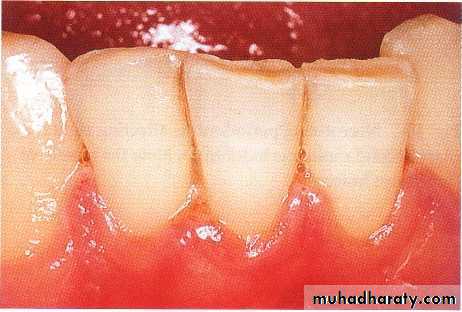

GINGIVITIS ASSOCIATED WITH POOR ORAL HYGIENE

Gingivitis associated with poor oral hygiene is usually classified as early (slight), moderate, or advanced.Early gingivitis is quickly reversible and can be treated with a good oral prophylactic treatment and instruction in good toothbrushing and flossing techniques to keep the teeth

free of bacterial plaque.

Gingivitis is generally less

severe in children than in

adults with similar plaque

levels.